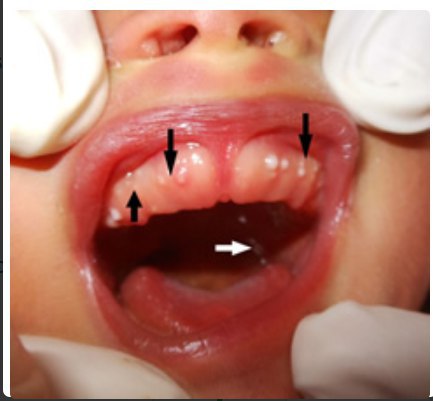

Микропост об узелках Бона

У детей первых месяцев жизни бывают мелкие белые жемчужные плотные узелки на деснах, самих детей они никак не беспокоят. Это узелки Бона. Еще бывают такие же на твердом небе - это жемчужины Эпштейна (почти одно и то же).

Это безопасно, бывает у 3 из 4 младенцев, проходит само и лечить не надо.

Это совершенно бесполезная информация, и я ни за что не стал бы про нее писать. Но коллеги уже просто достали пугать молодых матерей, называя это то стоматитом, то молочницей, то неонатальными зубами и назначая агрессивное лечение (холисал-калгель-кандид-кстоматологуудалять-самипроткнитеиголкой-сядьтенадиетубезкальция и еще много фейспалмов). Поэтому ознакомьтесь и запомните: ЭТО НЕ НАДО ЛЕЧИТЬ! Спасибоизвините